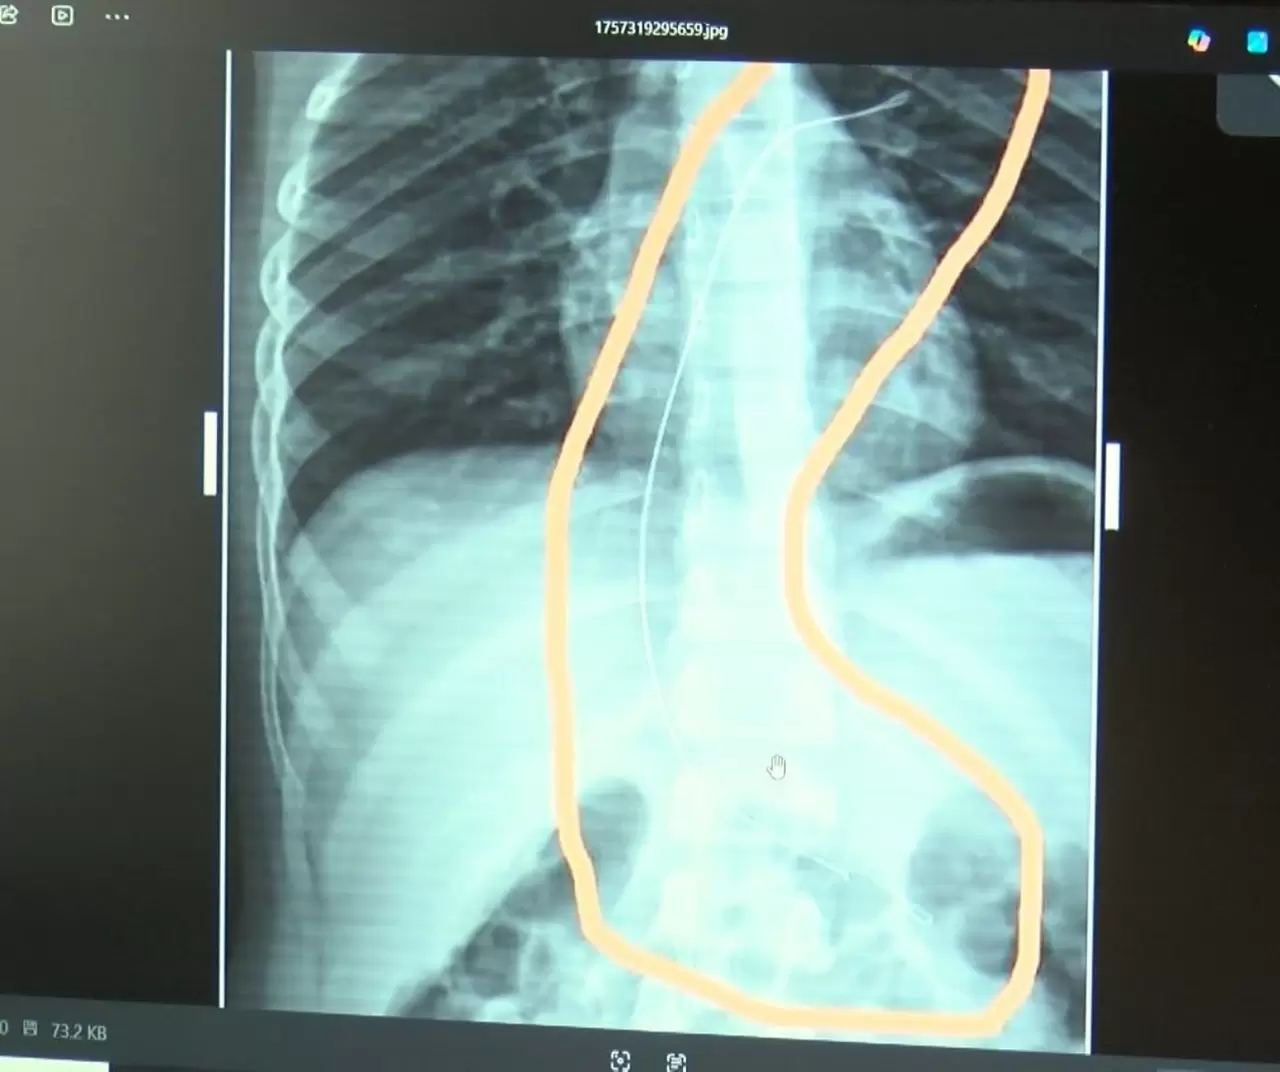

Şırnak’ta piknikte salatalık parçası yuttuktan sonra öksürük ve kusma şikayetleriyle hastaneye götürülen 6 yaşındaki Aram Devran Ötün’ün, 3 yıl önce Stevens- Johnson sendromu nedeniyle tedavi gördüğü sırada damar yoluna takılan 18 santimetrelik kateterin vücudunda unutulduğu ortaya çıktı. Öğüt, 5,5 saat süren riskli bir ameliyatla kateterden kurtuldu.

Şırnak’ta yaşayan 37 yaşındaki Semra ve 40 yaşındaki Mehmet Ötün çiftinin oğulları Aram Devran Ötün, mayıs ayında piknikteyken salatalık parçası yuttuktan sonra öksürük ve kusma şikayetleri görülünce Şırnak Devlet Hastanesi’ne götürüldü. Burada çekilen röntgen ve MR’da Aram’ın vücudunda kateter unutulduğu görüldü. Diyarbakır’daki Gazi Yaşargil Eğitim ve Araştırma Hastanesi Kadın Doğum ve Çocuk Ek Binası’na sevk edilen Aram, 5,5 saat süren riskli bir ameliyata alınarak 18 santimetre uzunluğundaki kateter çıkarıldı. Ameliyat sonrası yapılan incelemelerde kateterin kalp kapakçığına ve ciğerlerine zarar verdiği belirlendi.

”Çok riskli bir ameliyata alındı ve kateter çıkarıldı. Bu kateterin vücutta yol aldığı tespit edildi. İlk giriş yeri ve çıkarıldığı yer arasında çok fark var ve kalp kapakçığı ile ciğerlerine zarar verdiği tespit edildi. Müvekkillerimin hem maddi hem de manevi zararlarını karşılamak adına Dicle Üniversitesi’ne biz başvuruda bulunduk. 30 günlük cevap süresi içerisinde bize geri dönüş yapılmadı. Biz de maddi ve manevi zararların tazminat için Diyarbakır İdare Mahkemesi’ne davamızı açtık ve sorumlulardan şikayetçi olduk” dedi.

”Akşam 21.00 civarında acile götürdük. Röntgeni ve MR’ı çekildi. Tuhaf bir şey olduğunu anladık. Doktor röntgeni gösterdi. Tel kalmıştı. Çok kötü bir şekilde. Acil doktoru film çektikten sonra bize bir tel parçasını gösterdi. Bizi bekletmeden Diyarbakır’a sevkimizi verdiler. Diyarbakır Gazi Yaşargil Eğitim ve Araştırma Hastanesi Kadın Doğum ve Çocuk Ek Binası’na gittik. Çocuğun kasıklarından anjiyo yolu ile teli çıkaracaklarını ama riskli bir ameliyat olduğunu söylediler. O süreçte çocuk gerçekten sürekli yoruluyordu. İkide bir oturuyordu. ‘Anne çok yoruldum, karnım ağrıyor’ diyordu. Ben ağrı kesiciler ile geçiştirmeye çalışıyordum. Bu telin 3 yıl boyunca çocuğumda kaldığını öğrendim. Ailece yıkıldık” diye konuştu.